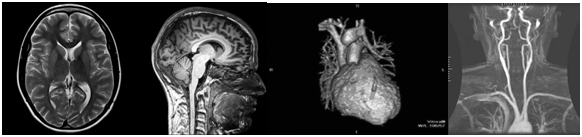

Magnetic Resonance Imaging(MRI)

ChandanDignostic Diagnostic Centre has 1.5 Magnetic Resonance Imaging(MRI) which is a medical imaging technique used in radiology to form pictures of the anatomy and the physiological processes of the body in both health and disease. MRI does not involve X-rays and the use of ionizing radiation, which distinguishes it from CT or CAT scans. Magnetic resonance imaging is a medical application of nuclear magnetic resonance (NMR).

Neuroimaging

MRI is the investigative tool of choice for neurological cancers, as it has better resolution than CT and offers better visualization of the posterior fossa. The contrast provided between grey and white matter makes MRI the best choice for many conditions of the central nervous system, including demyelinating diseases, dementia, cerebrovascular disease, infectious diseases, and epilepsy. Since many images are taken milliseconds apart, it shows how the brain responds to different stimuli, enabling researchers to study both the functional and structural brain abnormalities in psychological disorders. MRI also is used in guided stereotactic surgery and radiosurgery for treatment of intracranial tumors, arteriovenous malformations, and other surgically treatable conditions using a device known as the N-localizer.

Cardiovascular

Cardiac MRI is complementary to other imaging techniques, such as echocardiography, cardiac CT, and nuclear medicine. Its applications include assessment of myocardial ischemia and viability, cardiomyopathies, myocarditis, iron overload, vascular diseases, and congenital heart disease.

Angiography

Magnetic resonance angiography (MRA) generates pictures of the arteries to evaluate them for stenosis (abnormal narrowing) or aneurysms (vessel wall dilatations, at risk of rupture). MRA is often used to evaluate the arteries of the neck and brain, the thoracic and abdominal aorta, the renal arteries, and the legs (called a "run-off").